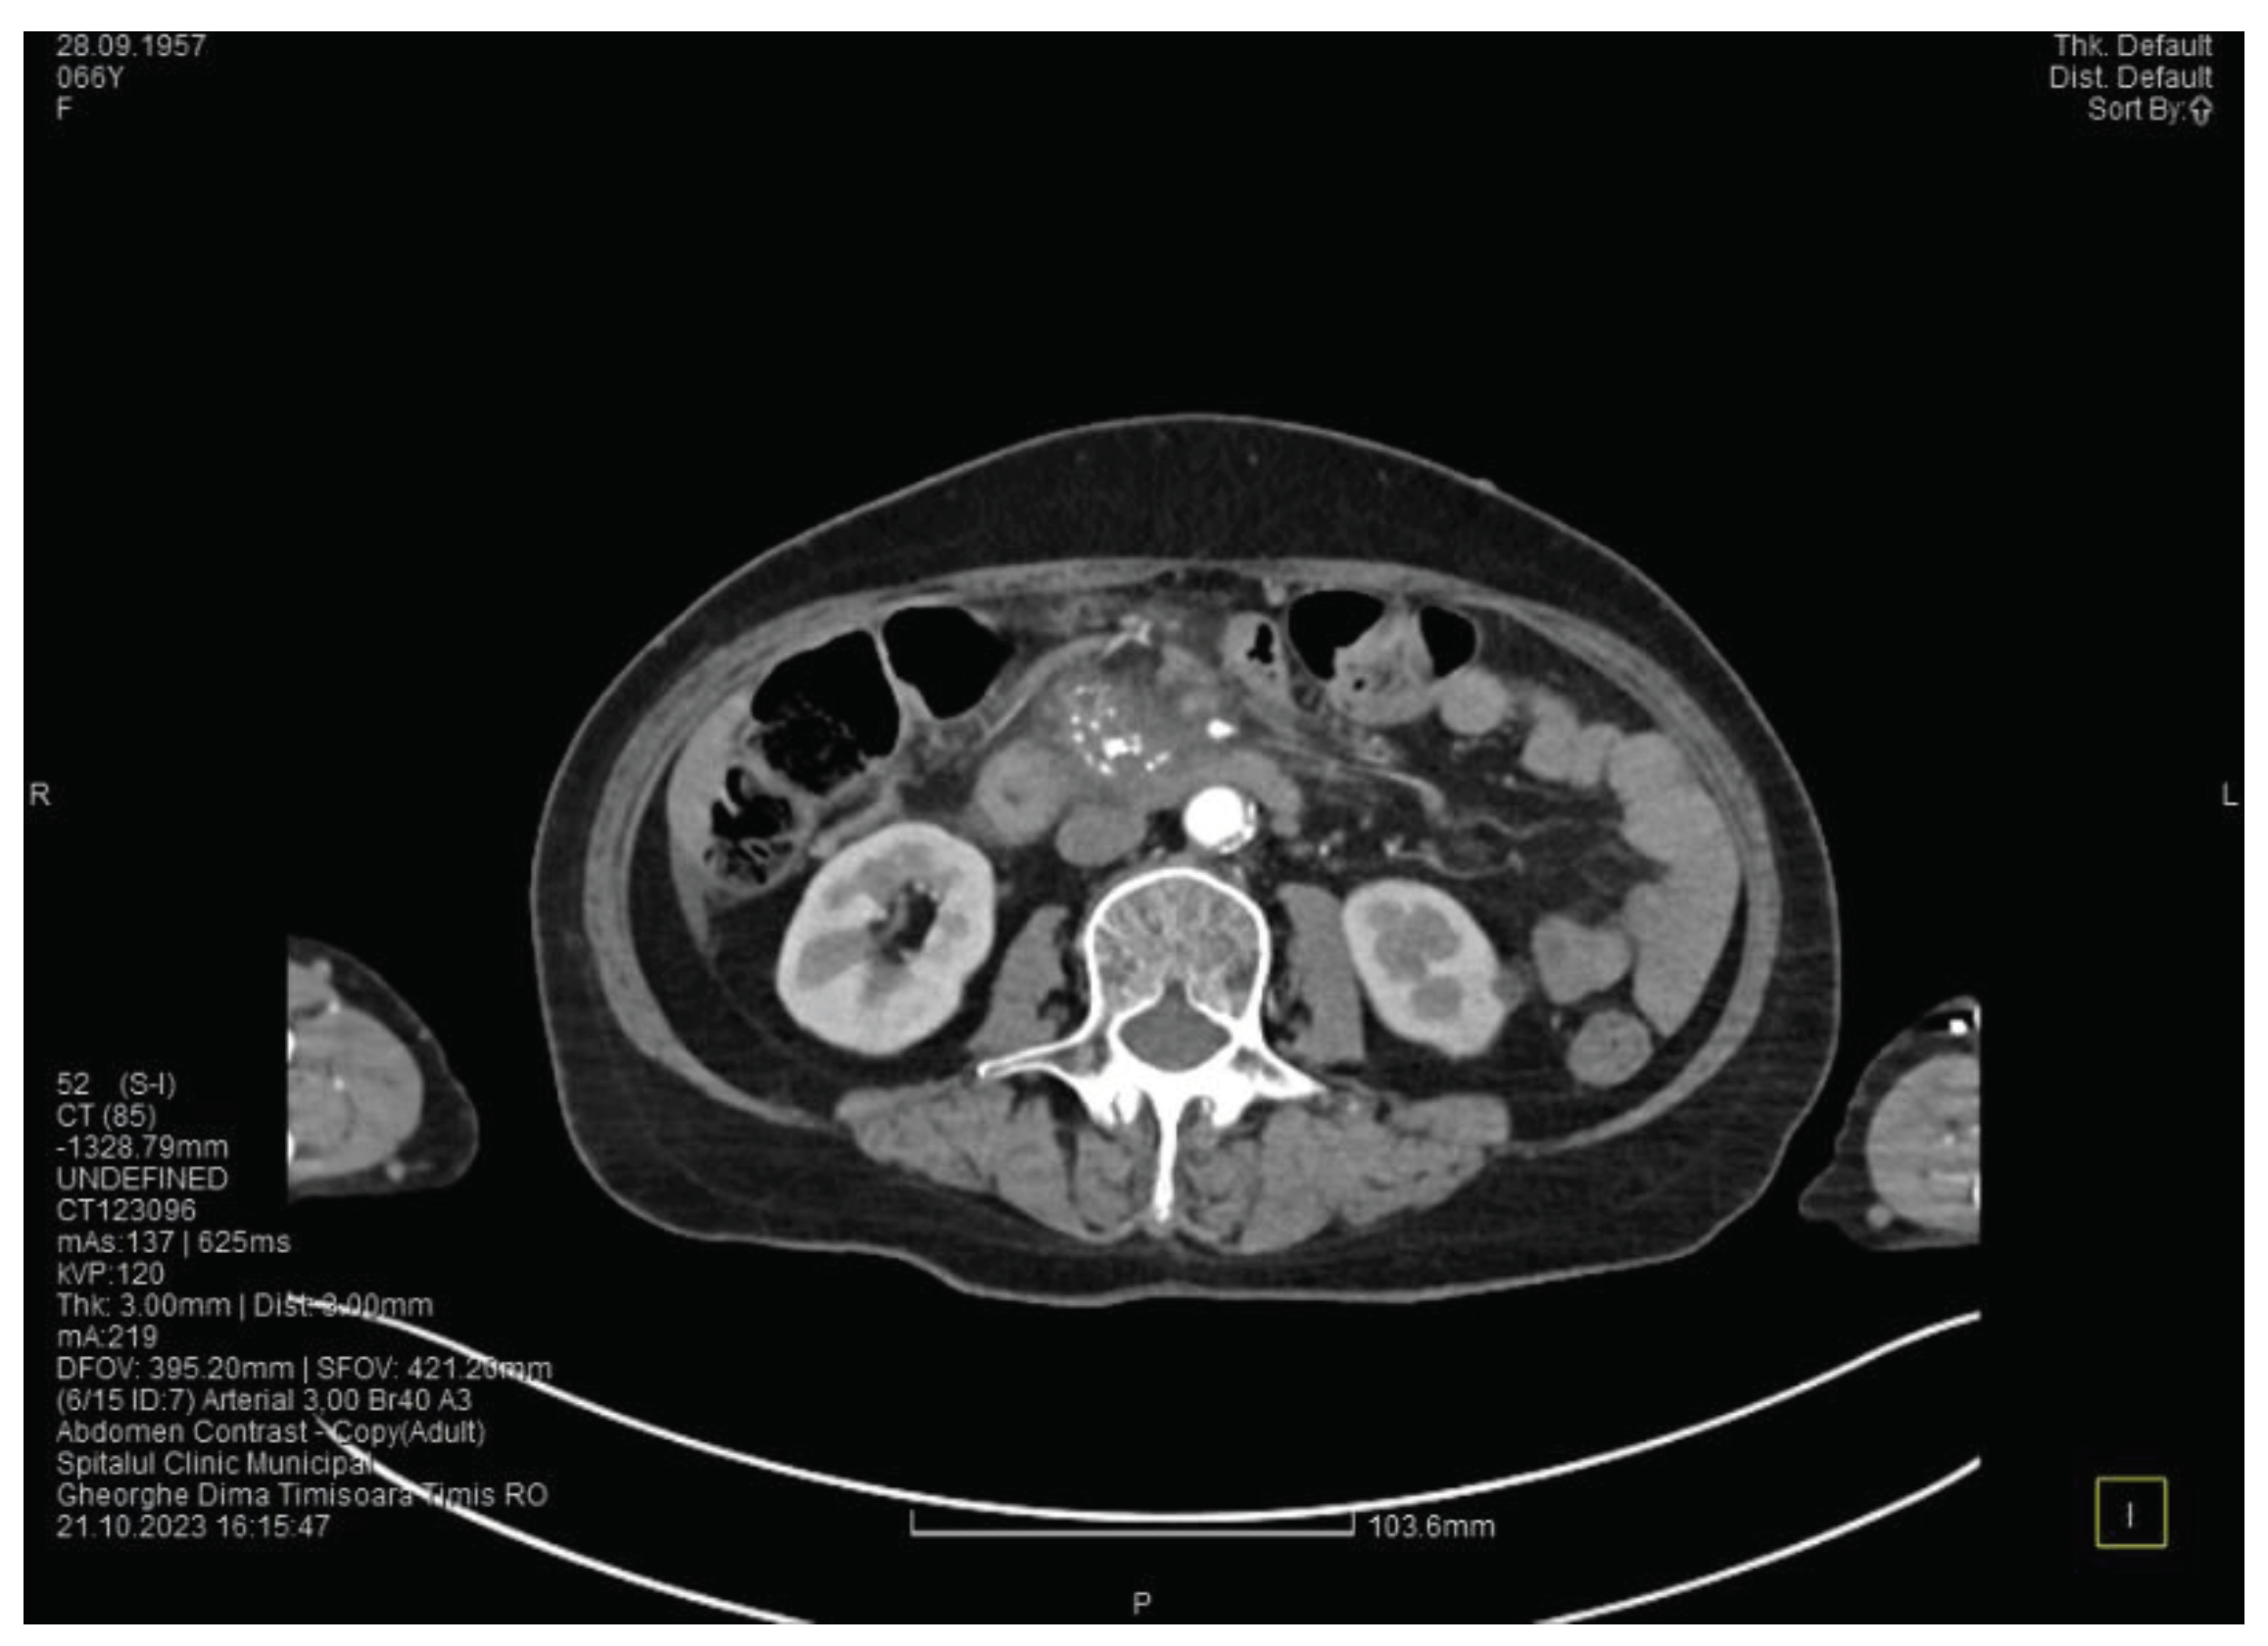

The contrast enhanced computed tomography showed changes suggestive for chronic pancreatitis, with multiple very small calcifications of the pancreatic tissue, a dilatation of the Wirsung duct in the corporeo-caudal area of approximately 15 mm (Figure 3) and a narrowing of the Wirsung tract in the cephalic area where calcareous conglomerates were present. In the anterior cephalo-uncinate area an oval cyst sized 31/28 mm is detected (larger than one month ago) (Figure 4). In the peri-cephalo-uncinate area we observed densifications of the adjacent fat extended towards the gastric antrum, the root of the mesentery and the hepatic flexure of the colon. There was a mild inflammatory enlargement of the peripancreatic lymph nodes and of the ons situated in the hepatic hilum. We also noticed a slight dilatation of the intrahepatic bile ducts and of the common hepatic duct and diffuse atheromatosis of the aorta, the iliac, and the common hepatic arteries. A gastroscopy is performed, which reveals normal esophagus, stomach and duodenal bulb.

Figure 3. The second CT evaluation shows a dilated Wirsung duct and calcifications in the pancreatic tissue.